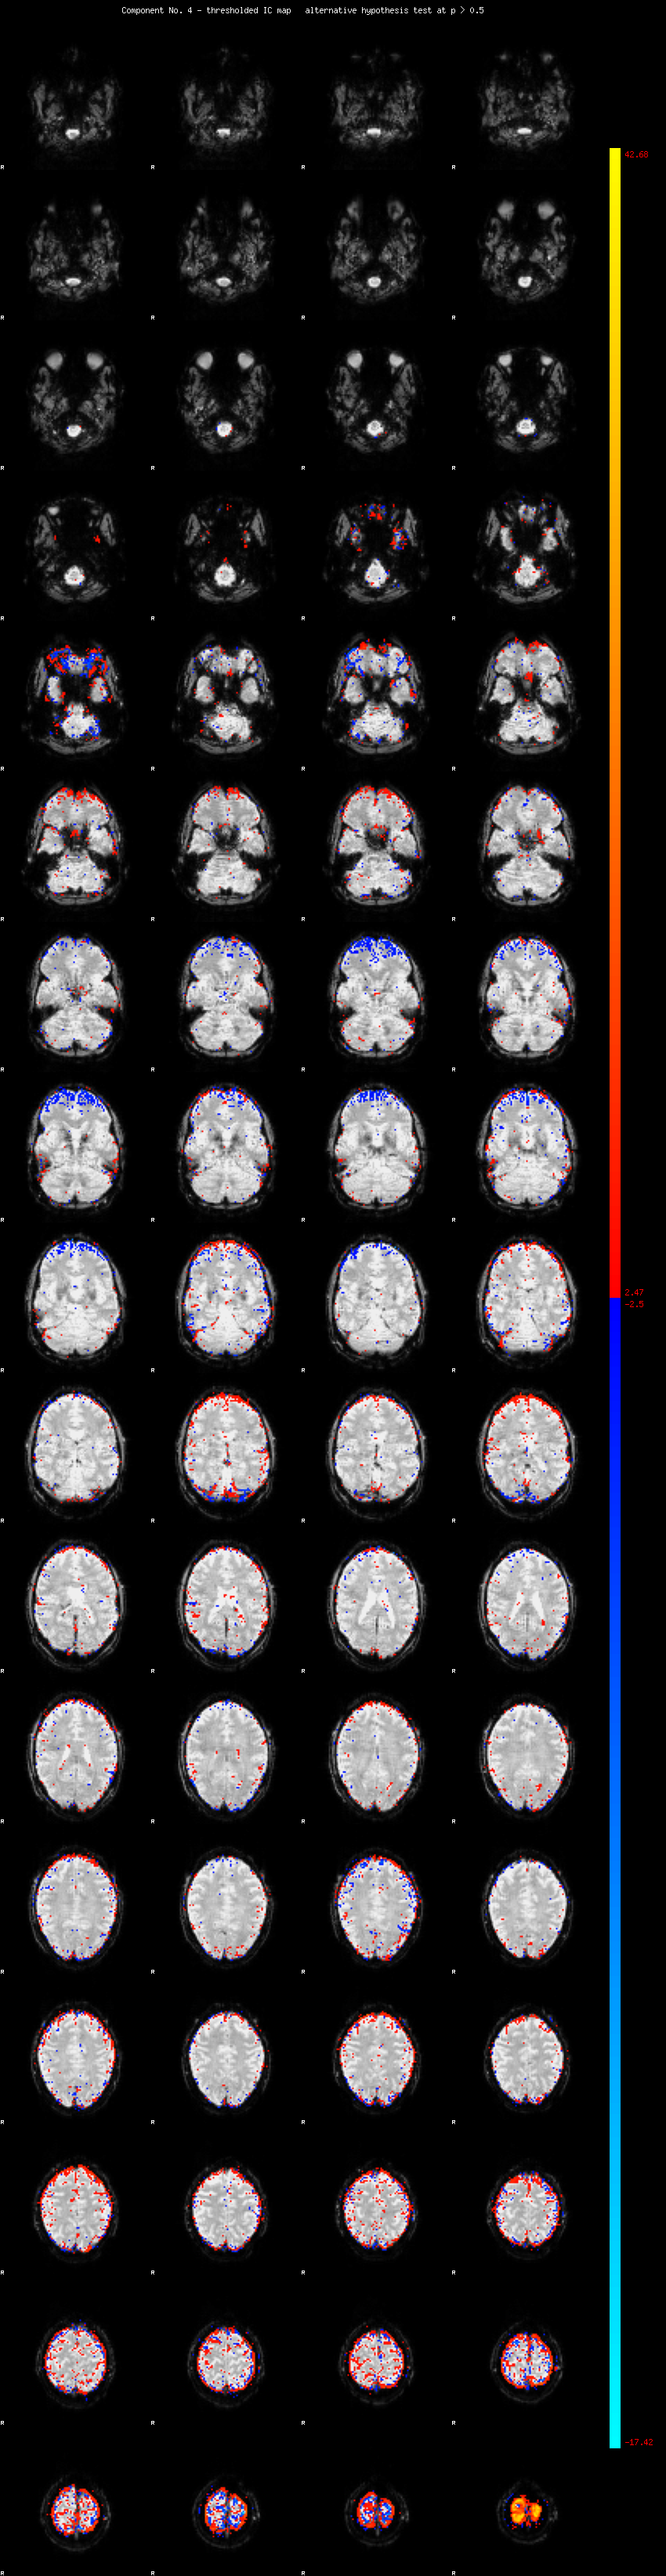

MELODIC Component 4

2.66 % of explained variance;     1.76 % of total variance